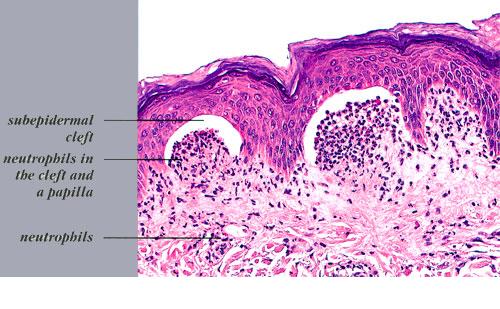

. The typical histologic features are best observed in erythematous skin adjacent to early blisters. In these zones, neutrophils accumulate at the tips of dermal papillae. With an increase in size to microabscesses, a significant admixture of eosinophils may be noted. As microabscesses form, a separation develops between the tips of the dermal papillae and the overlying epidermis; thus, the early blisters are multiloculated . The presence of fibrin in the papillae may give them a bluish appearance. Within 1 to 2 days, the rete ridges lose their attachment to the dermis, and the blisters then become unilocular  and clinically apparent. At this time, the characteristic papillary microabscesses may be observed at the blister periphery. For this reason, the inclusion of perivesicular skin in the biopsy specimen is of

utmost value. The papillary dermis beneath the papillae may have a relatively intense inflammatory infiltrate of neutrophils and some eosinophils. Many neutrophils may exhibit leukocytoclasis. Subjacent to this, a perivascular infiltrate composed of lymphocytes, neutrophils, and eosinophils may be apparent. the diagnostic finding of papillary microabscesses may not be present in all patients. Apoptotic keratinocytes may be noted above the papillary microabscesses.